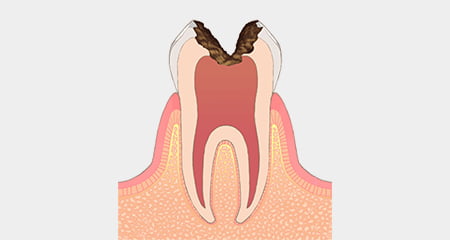

重度虫歯

虫歯が重症化して神経にまで達した段階を、歯髄炎や根尖性歯周炎といいます。この状態になると、歯に強烈な痛みを生じることがほとんどであるため、生活に悪影響が現れます。痛みのない場合は歯の下で症状が進行していき、歯髄が壊死しているケースもあります。

「歯が痛かったのに急に治まった」という場合には、可能な限り早く治療を受けることをご検討ください。progress

残根

重度の虫歯の進行が進み、歯茎から上の歯がほとんど解けてしまって、歯の根の部分だけが残った状態を、残根(ざんこん)といいます。根管と呼ばれる歯の根の内部に細菌が繁殖しており、感染した組織を取り除くことはほぼ不可能です。

患部から細菌が体内に入り込むのを防ぐために、抜歯するケースが多くみられます。